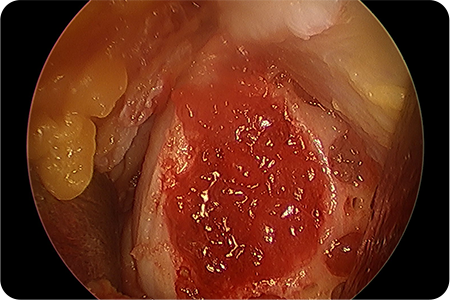

3. 카티스템 줄기세포 도포·이식

제대혈 유래 줄기세포를 손상된 연골 부위에 직접 도포하거나 이식합니다.